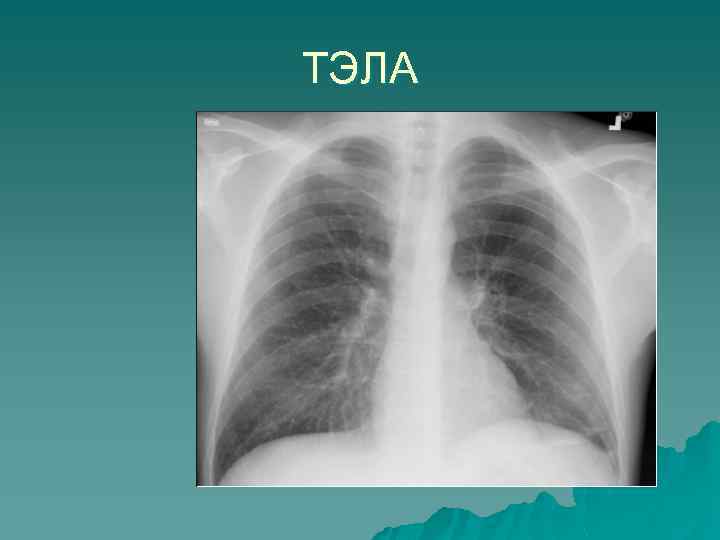

Гипоксемия «Белая» рентгенограмма Отек легких ОРДС Вирусная пневмония Жировая эмболия Пневмония Ателектазы «Черная» рентгенограмма Обострение ХОБЛ ТЭЛА Микроателектазы

ТЭЛА